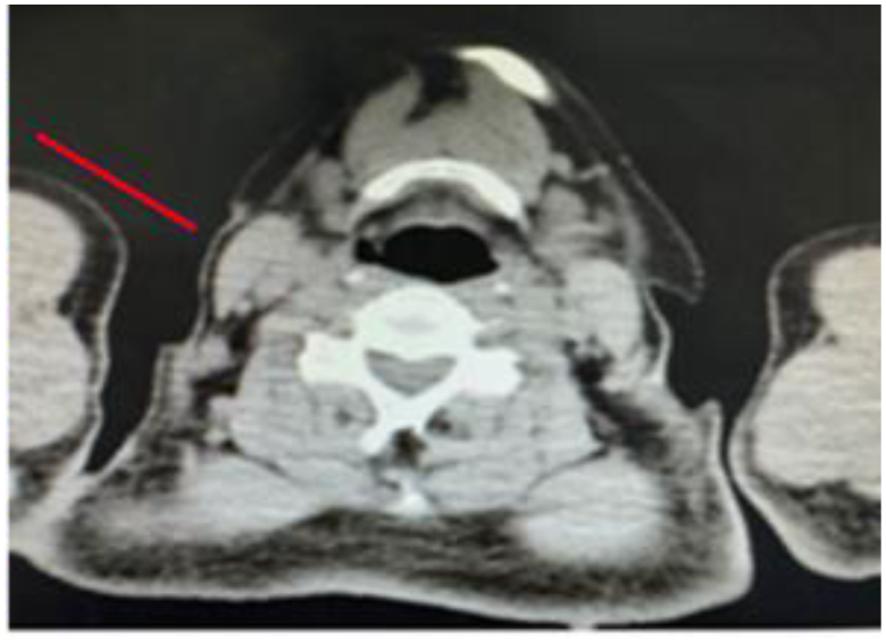

Figure 4

A mass can be seen in the right cervical region, with surrounding tissues compressed and displaced, and is indicated by the red arrow.